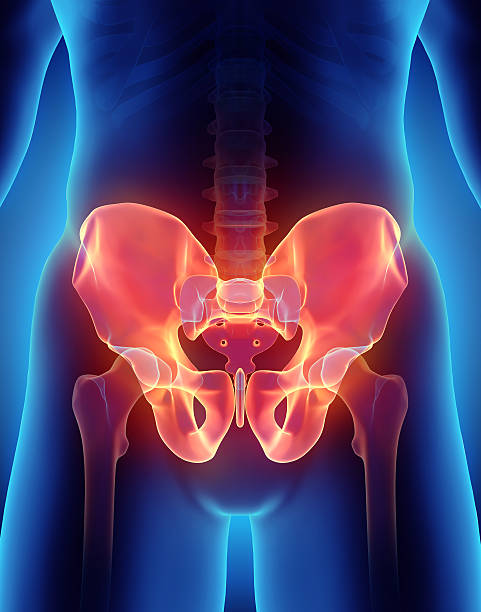

골반은 복부 하단에 위치하고 있는데 양쪽의 2개 볼기뼈와 후단부의 천골(엉치뼈)와 미골(꼬리뼈)로 구성되어 있으며 척추 부분과 하지를 연결하여 체중을 지탱하며 각종 내장과 자궁, 난소, 방광 등 주요 장기를 외부 충격에서 보호할 수 있습니다.